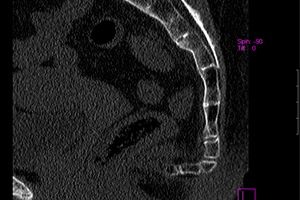

A coccyx radiográfiája. A standard vizsgálatot egy egyenes vonalban (egyenes lábon fekvő fekvő helyzetben) és oldalirányban (oldalirányban hajlított lábakkal) vetítik. A roentgenogramon nem mindig látható a törés, hiszen a coccyx kis csontjai eltakarják a lágy szövetek sorát.

A gerinc tomográfiája. A leginkább informatív módszer, amely lehetővé teszi a sűrű struktúrák részletes kidolgozását.